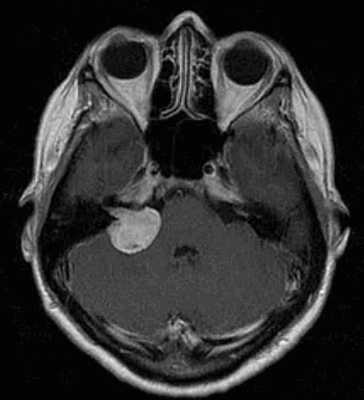

Наиболее информативным методом выявления вестибулярных шванном является МРТ головного мозга с контрастным усилением в режиме Т1 и Т2. Это исследование позволяет определить размеры опухоли, наличие перитуморозного отека, наличие признаков окклюзионной гидроцефалии, которая может быть следствием сдавления опухолью IV желудочка. Кроме этого МРТ позволяет провести дифференциальную диагностику с другими опухолями схожей локализации (чаще с менингиомой задней грани пирамиды височной кости). Еще одним стандартом диагностики является КТ в костном режиме. Независимо от снижения слуха стандартом является проведение аппаратной аудиографии.

- Магнитно-резонансная томография (МРТ).

Если предыдущие исследования с большой долей вероятности указывают на шванному, наиболее информативным инструментальным методом визуализации считается МРТ. Это современное высокоточное неинвазивное исследование, которое позволяет определить размер и локализацию опухоли, а также увидеть состояние окружающих ее органов и тканей. Магнитно-резонансная томография проводится по назначению лечащего врача или по желанию пациента при наличии головных болей, головокружений, при подозрении на опухоль (ухудшение зрения, слуха, нарушение речи, чувствительности и движений в конечностях).

После проведения основной МР томографии может понадобиться уточняющее исследование для постановки дифференциального диагноза, уточнения размеров опухолевого процесса и степени вовлечения окружающих органов и структур. В таком случае назначается МРТ с контрастным усилением, в ходе которого в вену пациента вводится контрастное вещество. Изображения, полученные с применением контраста, дают не только точное представление о размере и границах невриномы, но позволяют оценить функциональные нарушения в органах.

До начала радиохирургического лечения проводится обследование, позволяющее определить точное положение опухоли и прилегающих нервных образований. Выполняется трехмерная реконструкция, отображающая детальную микрохирургическую анатомию этой области. Для этой цели с помощью МРТ получают четкую визуализацию опухоли и нервов во внутреннем слуховом проходе и области мосто-мозжечкового угла.